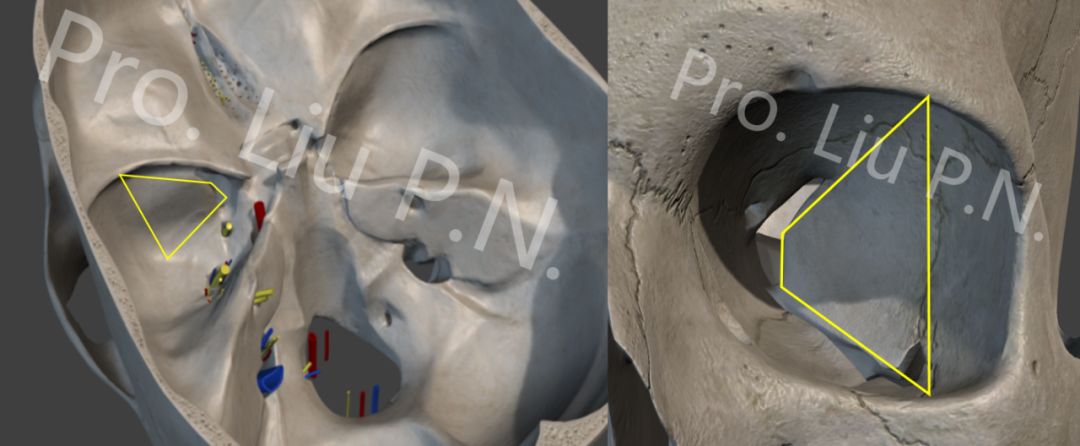

十三、经眶外侧壁入路内镜解剖

![]()

左眼眶皮肤切口

向内侧牵开眶内容物

磨除眶外侧壁

切除颞极前方硬膜

十四、内镜经眶外侧壁入路适应症

内镜经眶外侧壁入路是近年探索的新的到达海绵窦区手术入路,已有文献证实期解剖合理性,但是在国内外应用均不多,仍处于临床探索阶段,该入路可能存在眼球过度牵拉和视神经损伤风险,但单纯从解剖角度来看,通过磨除眶外侧壁可以充分的显露颞极和海绵窦外侧壁,对于体积较小的窦旁肿瘤可能是一种不错的选择